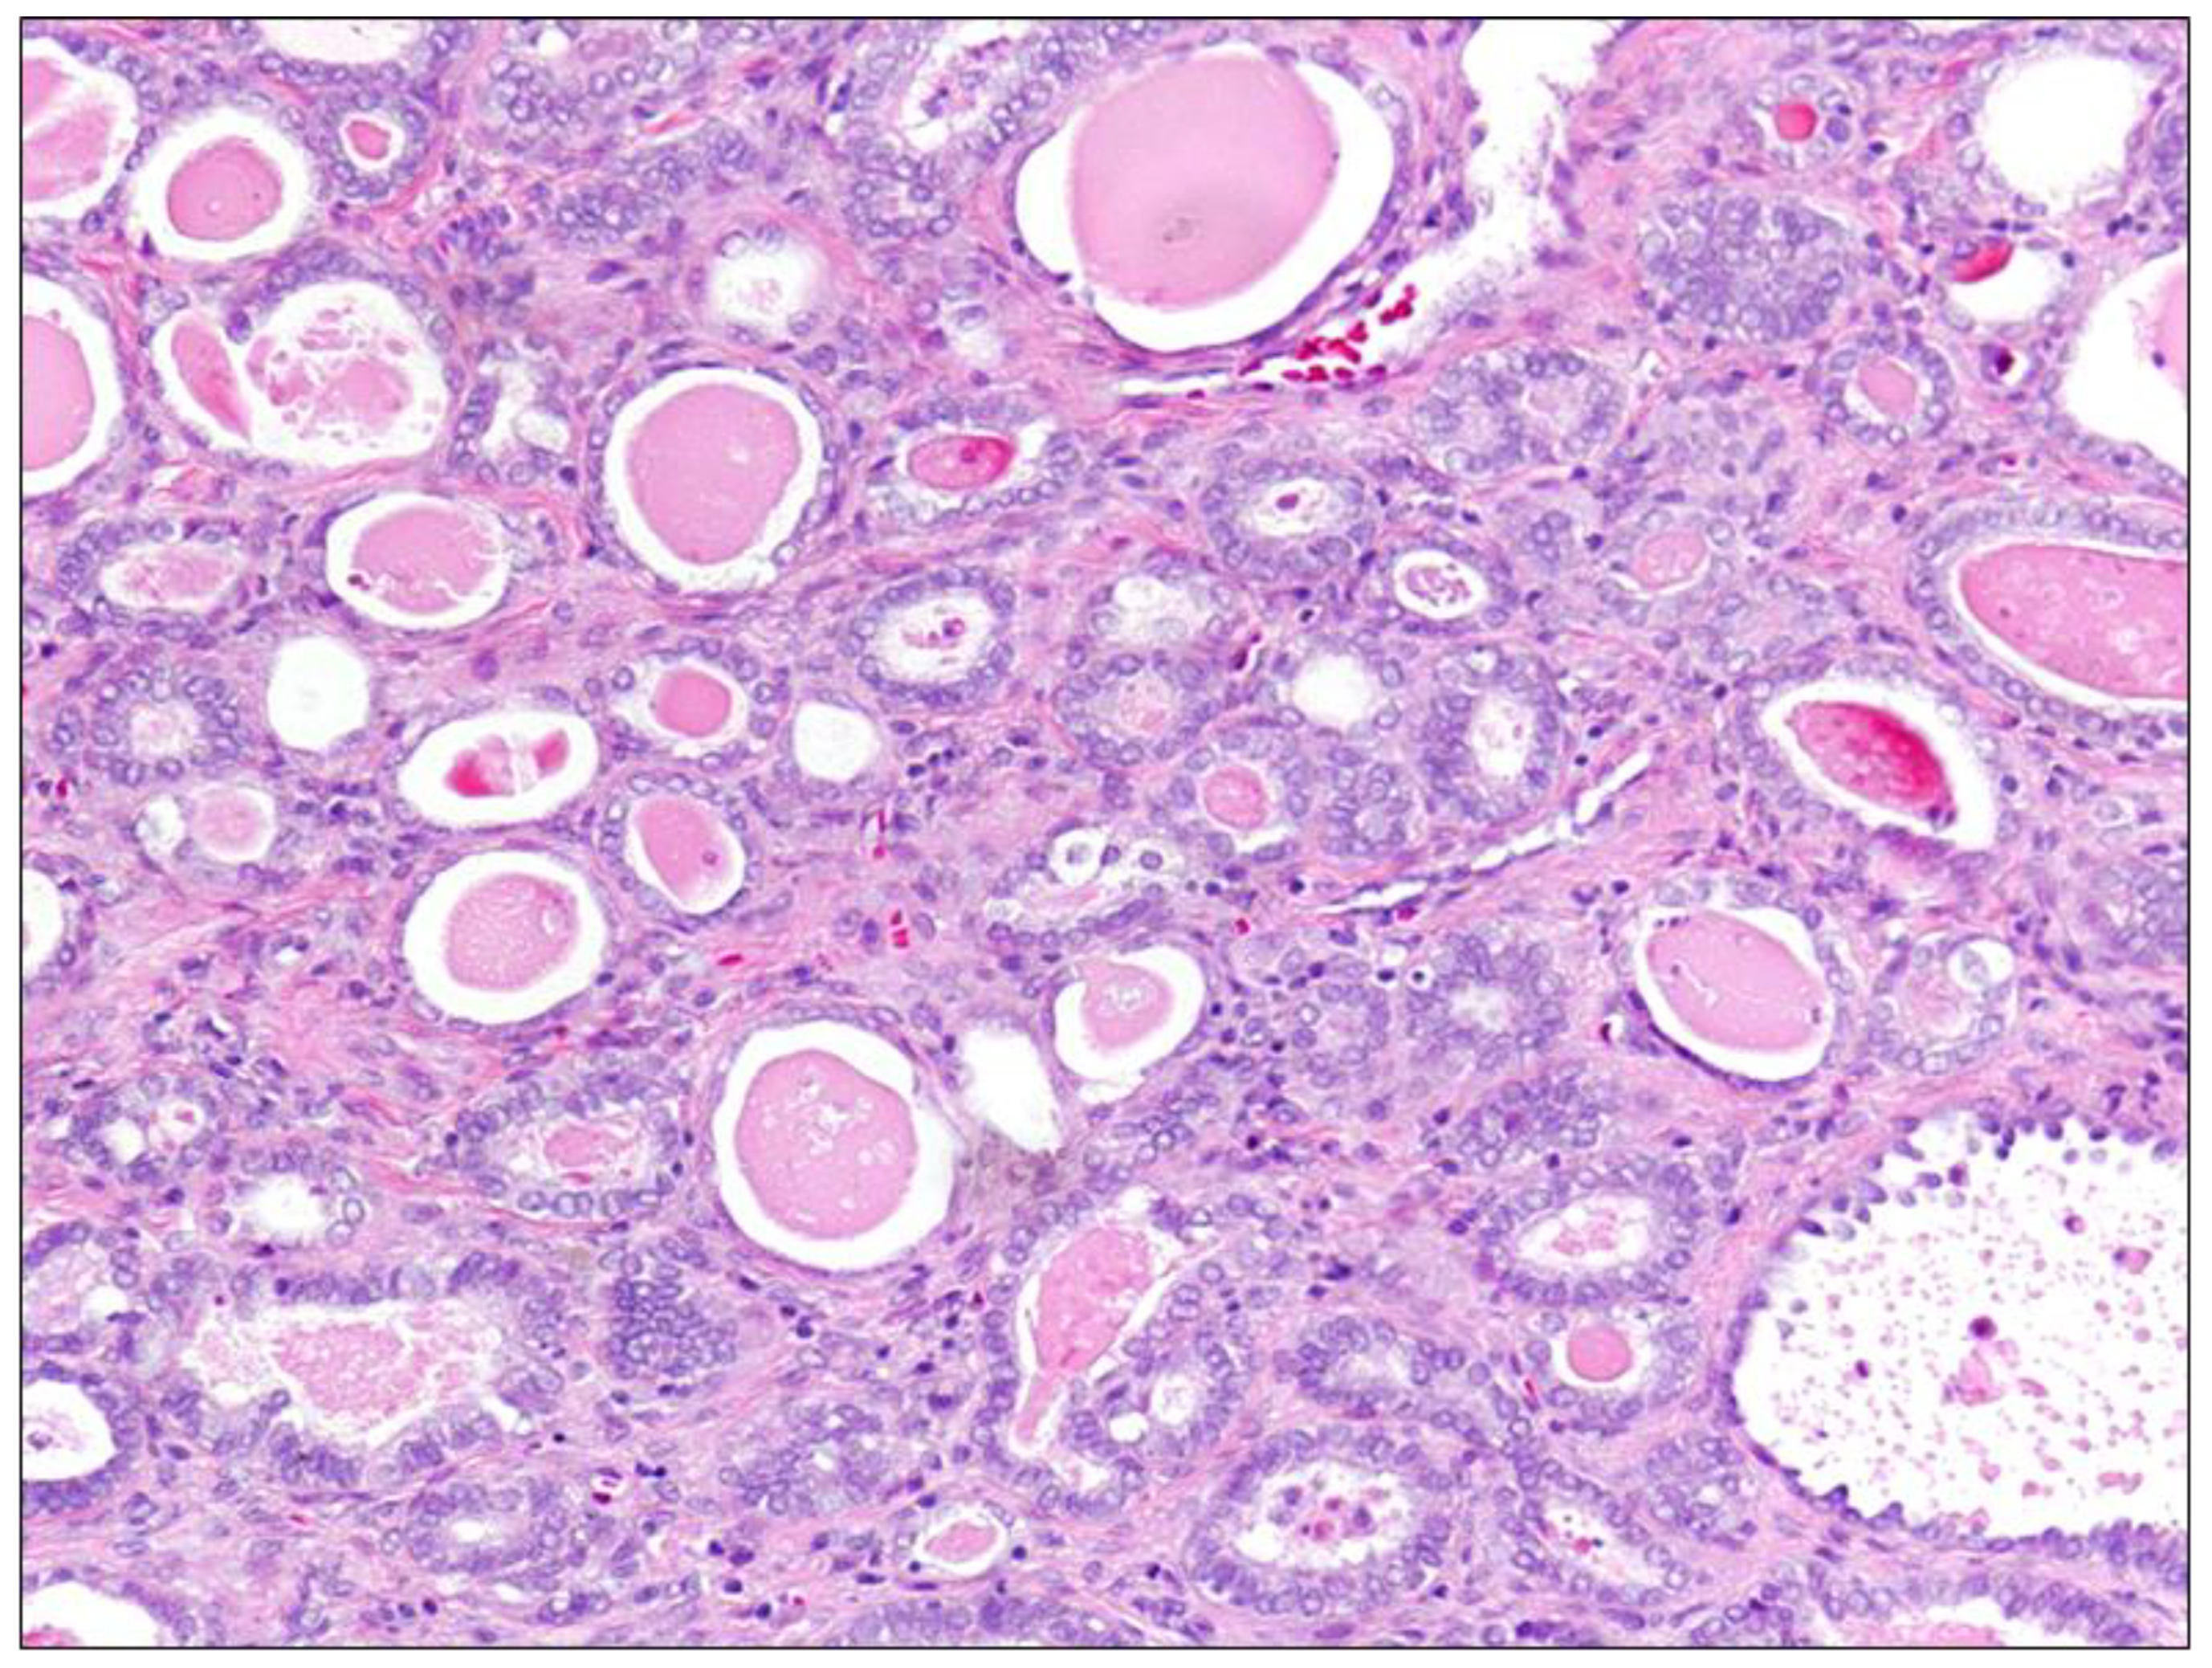

3.1.2. Mesonephric Endocervical ADC

Mesonephric endocervical ADC (Figure 2) arises from mesonephric ductus remnants or mesonephric hyperplasia areas. It is a rare tumor, and in several reports it had appeared not to be associated with high-risk HPV [24]. These tumors commonly grow in the lateral to posterior cervical wall and may be deeply invasive and either bulky or exophytic. These may display a variety of histopathological patterns, including tubular glands lined by mucin-free cuboidal epithelium containing eosinophilic secretion within their lumina. Other patterns include papillary, solid, ductal, and spindle cell [20,25]. Mesonephric ACS may be reactive for cytokeratin and epithelial membrane antigens, often expressing calterinin, CD10, and vimentin. Typically, this tumor is negative for estrogen and progesterone receptors and CEA, but may express PAX8 and focally p16 [6].

Figure 2. Mesonephric carcinoma, Hematoxylin-Eosin, 20× magnification. This panel shows a typical mesonephric carcinoma composed of tubular glands lined by mucin-free cuboidal epithelium containing eosinophilic, hyaline secretion in their lumina. Haphazard infiltrative growth, elevated mitotic activity, the presence of intraluminal cellular debris, and nuclear atypia are also peculiar features.